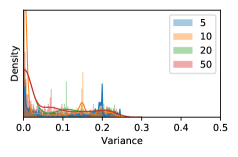

To model how different classifiers will respond to a given input , we assume that the prediction from classifier is sampled from a beta distribution that is characterized by two parameters by and . We further assume that is fixed to the same constant value for all ’s. Under this assumption, each input can be described by ( can be calculated since is fixed), easing further analysis. The Severity Level (SL) of the case represented by image can be characterized by the parameter . The larger the value of , the more severe the case of is. When and are close, the case is ambiguous as the distribution shifts towards being symmetric (i.e. signifying much disagreement among classifiers) rather than being one-sided (i.e. consensus among classifiers that is negative or positive). We provide a set of examples in Figure 2 and also Figure S.8 in the supplementary materials showing how the beta distribution can be used to capture diverse predictions given by an ensemble learner.

In contrast, the MC-dropout method showed the worst overall performance among the three, as it can be seen from the high ratios of SL0 examples among the uncertain negatives in Figure 4. The histograms in Figure 2 provides another perspective to look into the phenomenon, where a decent proportion of MC-dropout model’s predictions on SL0 inputs entailed low confidence (far from 0 or 1), which from another angle explained why MC-dropout was less specific in terms of lower FNP; many no-DR inputs (i.e. SL0) were erroneously assigned high uncertainty by MC-dropout models.

As discussed in Section 5.1 and Section 5.3 in the main paper, the mean metric and the stacking ensemble will have better performance in the precision (specificity) on the ambiguous data. Here, more detailed results are shown in Figures S.3 & S.6 and Table S.1. Figures S.3 & S.4 show the histograms of the uncertainty score for Kaggle-DR and Messidor-2 datasets that are the in-distribution (i.d.) dataset in our experiment and FigureS.5 & S.6 show the histograms for ImageNet and CIFAR-10 datasets, which is the o.o.d. datasets in our experiment. Each group of histograms contains results from the three evaluated ensemble methods (stacking ensemble, MC-dropout and TTA) and the three uncertainty metrics (mean, var and kl). Additional detailed results not displayed in Figure 4 can be found in Table S.1, which shows the proportion of the data of different SLs varies across different . For comparison, we also included in Table S.1 the results from single learners, and the proportions of data of different SLs (before any selection was made).